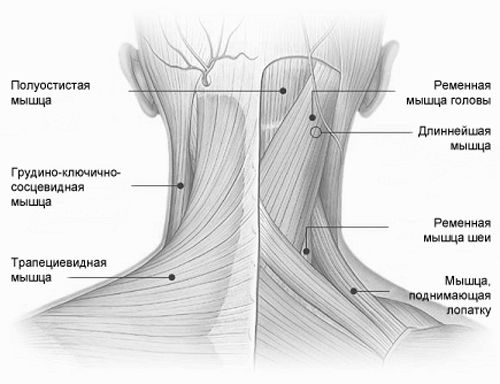

Типи потиличних м'язів

- Пекуча пульсуюча, в більш важких випадках стріляючий, одностороння, рідше двостороння, біль в районі нижньої частини шиї, в області потилиці (сосковидних відростків, а також потиличного бугра) і часто в очах і над ними (характерна для невралгії великого потиличного нерва) або за вухами і трохи нижче їх, у верхній частині грудино-ключично-соскоподібного м'яза (при патології малого нерва, що іннервує шкіру потилиці),

Хоча тривалість нападу зазвичай не перевищує кількох секунд, біль при невралгії потиличних нервів настільки сильна, що перешкоджає підтримці хворим звичайного ритму своєї життєдіяльності і змушує його прийняти неприродну позу з головою, відхиленої в сторону піддався поразки нерва і трохи назад, за рахунок напруги під час нападу м'язів шиї.